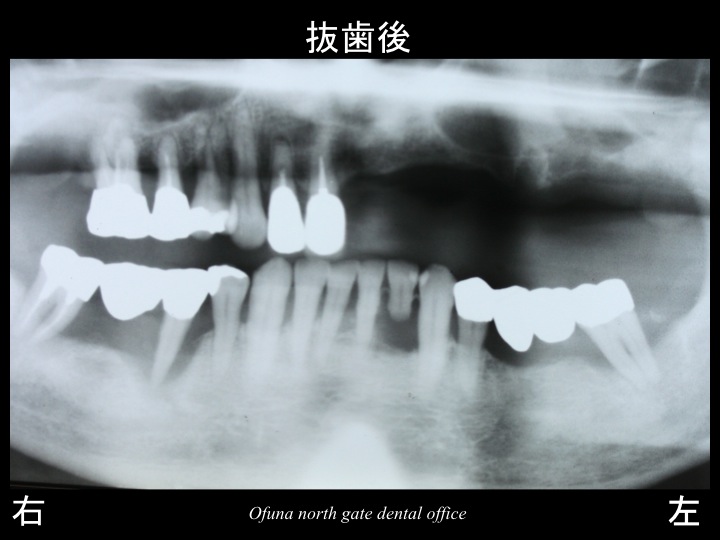

その結果、以下の歯を抜歯することにしました。

抜歯と判断した以外の歯は、徹底した歯周病治療 を行うことにしました。

以下は、上顎を抜歯した後です。

ここで注目したいのが、上顎左側の抜歯した穴です。

『 穴 』です。

この部分のみを拡大して見てしましょう。